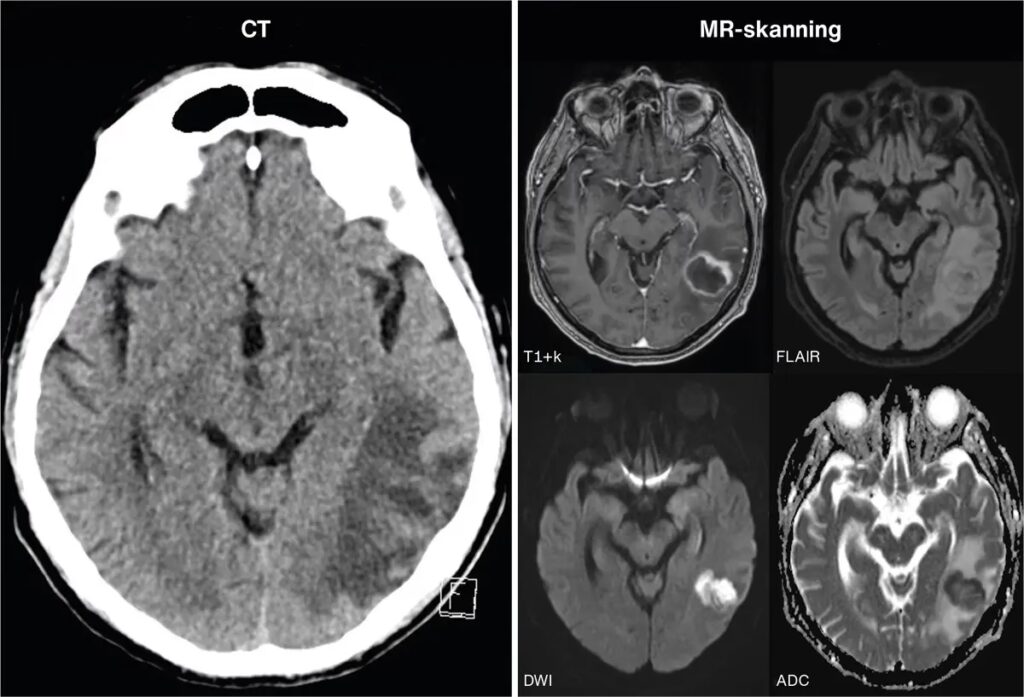

Hvis der er mistanke om en hjerneabsces, er hurtig handling afgørende. Lægen vil først foretage en grundig neurologisk undersøgelse for at vurdere reflekser, muskelstyrke, følesans og koordination. Den endelige diagnose stilles dog ved hjælp af billeddiagnostik:

- CT-scanning (Computertomografi): Ofte den første scanning, der udføres i en akut situation. Med kontrastvæske vil en hjerneabsces typisk vise sig som en karakteristisk ringformet struktur.

- MR-scanning (Magnetisk Resonans): Denne scanning giver mere detaljerede billeder af hjernen og er bedre til at identificere små eller tidlige abscesser samt den omkringliggende hævelse.

Blodprøver tages for at lede efter tegn på infektion i kroppen. I nogle tilfælde kan det være nødvendigt at udtage en prøve af pusset fra abscessen. Dette gøres ved en procedure kaldet stereotaktisk aspiration, hvor en tynd nål føres præcist ind i abscessen ved hjælp af CT- eller MR-vejledning. Prøven sendes til laboratoriet for at identificere den specifikke mikroorganisme, så behandlingen kan målrettes.